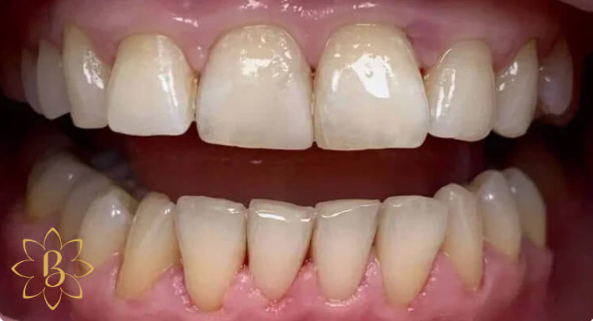

На странице представлено портфолио стоматологий Санкт-Петербурга с работами до и после профессиональной чистки зубов. В нашем портфолио собраны разные клинические случаи: от удаления незначительного налета до снятия массивного поддесневого камня. Здесь вы можете увидеть, как возвращается естественный цвет и внешний вид зубов после процедуры. Изучите результаты до и после чистки зубов, чтобы увидеть реальный эффект и выбрать клинику в Санкт-Петербурге, где профессиональная гигиена поможет вернуть зубам здоровый вид.

Профгигиена